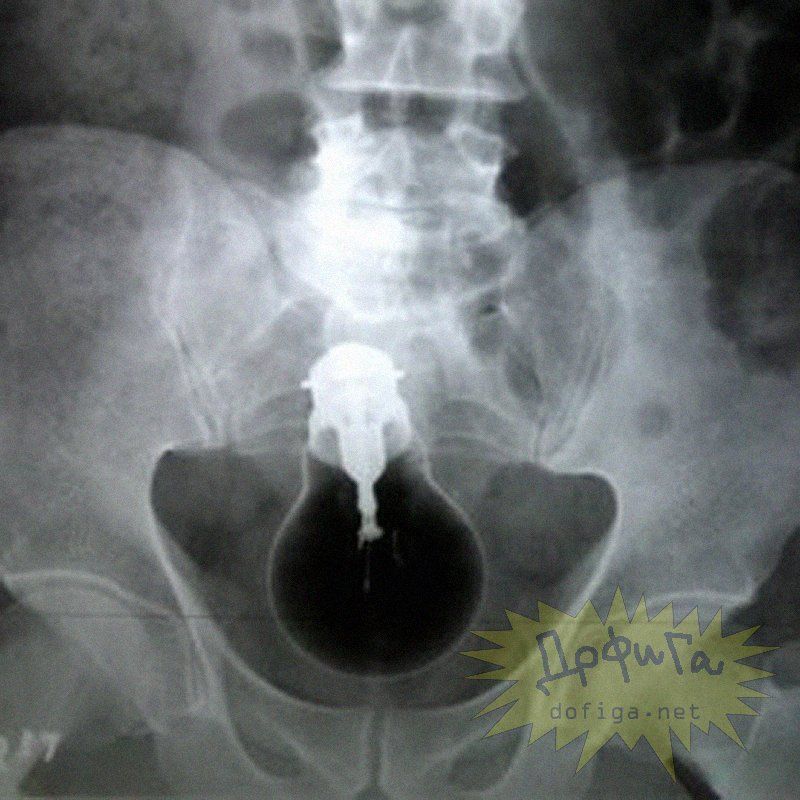

アナルに ”何かしら” を突っ込んで取れなくなってしまう人たちは意外に多いみたいで、そんな人たちのレントゲン写真を集めたギャラリー[13]images